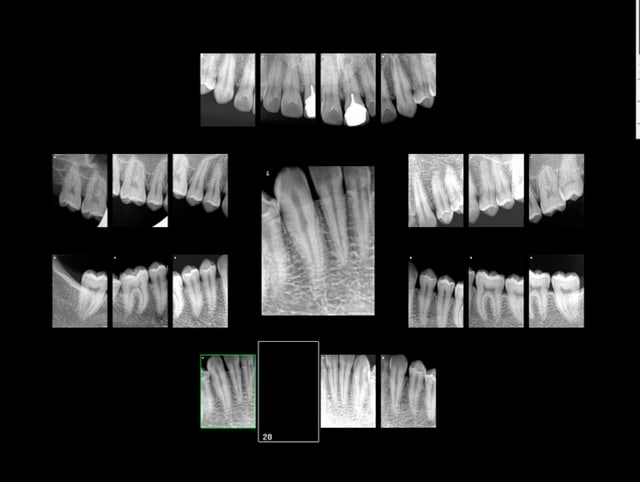

Cas concret : -)

Ca a marché je pense parce que c'était un bilan TIB complet. Radios injustifiables individuellement sauf une. -)